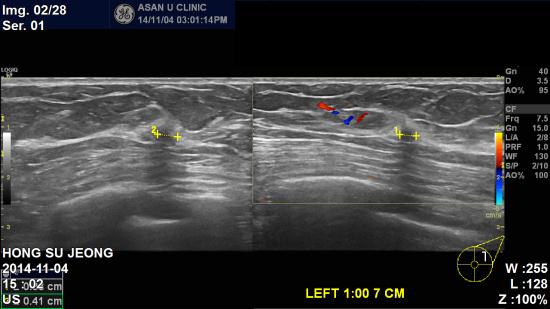

아산유외과 개원 후167번째 유방암진단

건강검진상 이상소견이 있어 조직검사 위해 의뢰된

57세 여성분입니다.

왼쪽유방 유두에서 7cm 떨어진 곳에 0.3cm 혹 발견되어

조직검사 진행하셨고 침윤성 소엽암 진단 받으신 분입니다

건강검진이 유방암의 발생을 예방하는 것이 아니라

조기에 진단할 수 있도록 도와주는 것이 최선입니다